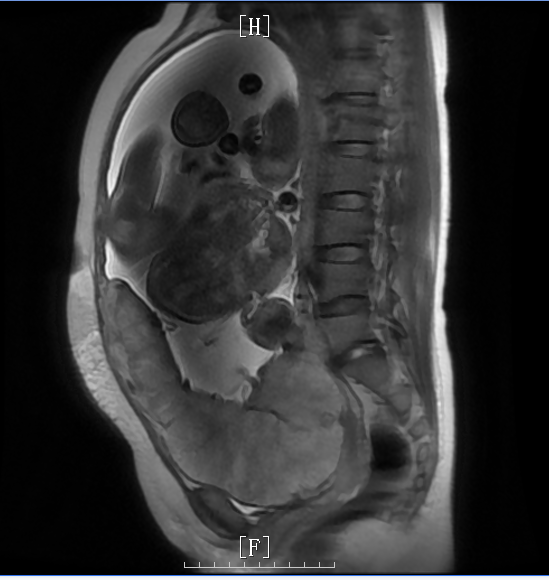

2023-10-23,我院胎盘MRI:晚孕;中央型前置胎盘,左侧壁局部胎盘植入可能(宫腔内见胎儿影,横位,胎盘位于子宫前壁、左壁、后壁,矢状位示宫颈内口后缘被完全覆盖,冠状位及横断位示胎盘左侧壁见局限性凸起,局部子宫肌层菲薄。宫颈未见明显异常信号。盆腔内未见软组织肿块或积液影。